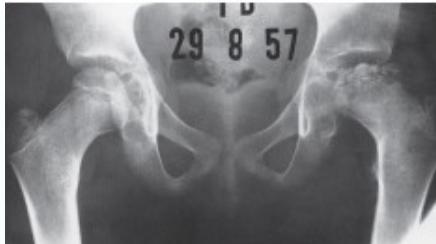

Radiographic Stages:

-

Initial/ Bone Death Stage (Sclerosis)

- May initially appear normal on x-ray

- Increased density followed by collapse

Revascularization and Repair Stage

- Reduced density and fragmentation on x-ray

Distortion and Remodeling Stage

- Distortion, flattening (coxa plana)

- Enlargement (coxa magna) with partial uncoverage

Radiological Progression:

Progression: Sclerosis → Collapse → Fragmentation → Remodeling

Imaging Examples: